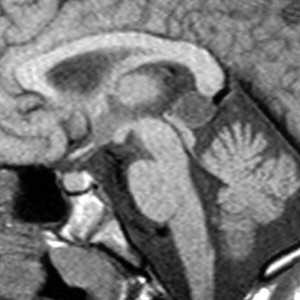

МРТ головного мозга. Сагиттальная Т1-взвешенная МРТ. Пинеальная киста.